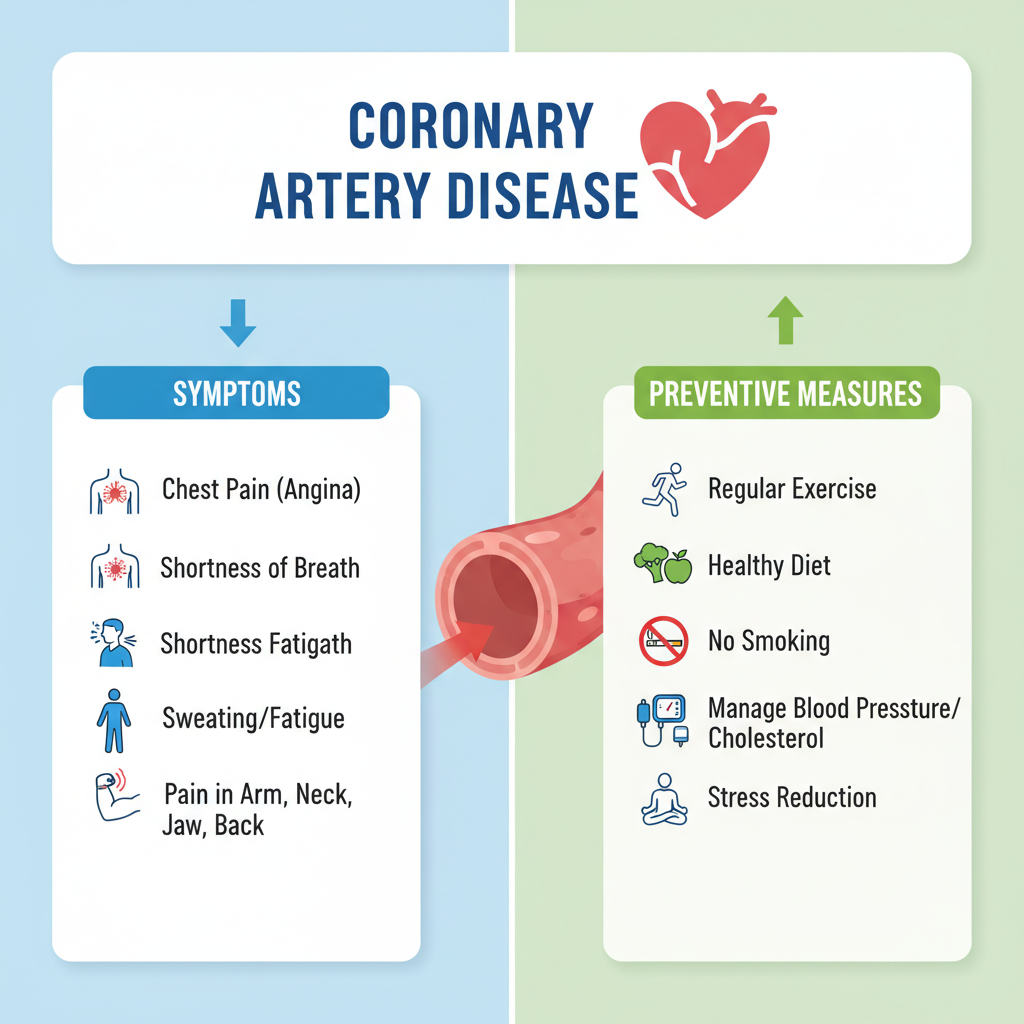

Bệnh mạch vành đang trở thành một trong những nguyên nhân hàng đầu gây tử vong hiện nay. Hiểu biết về bệnh và thực hiện các biện pháp phòng ngừa kịp thời sẽ giúp bạn bảo vệ sức khỏe tim mạch của mình.

Bệnh mạch vành đang trở thành một trong những nguyên nhân hàng đầu gây tử vong hiện nay. Hiểu biết về bệnh và thực hiện các biện pháp phòng ngừa kịp thời sẽ giúp bạn bảo vệ sức khỏe tim mạch của mình.